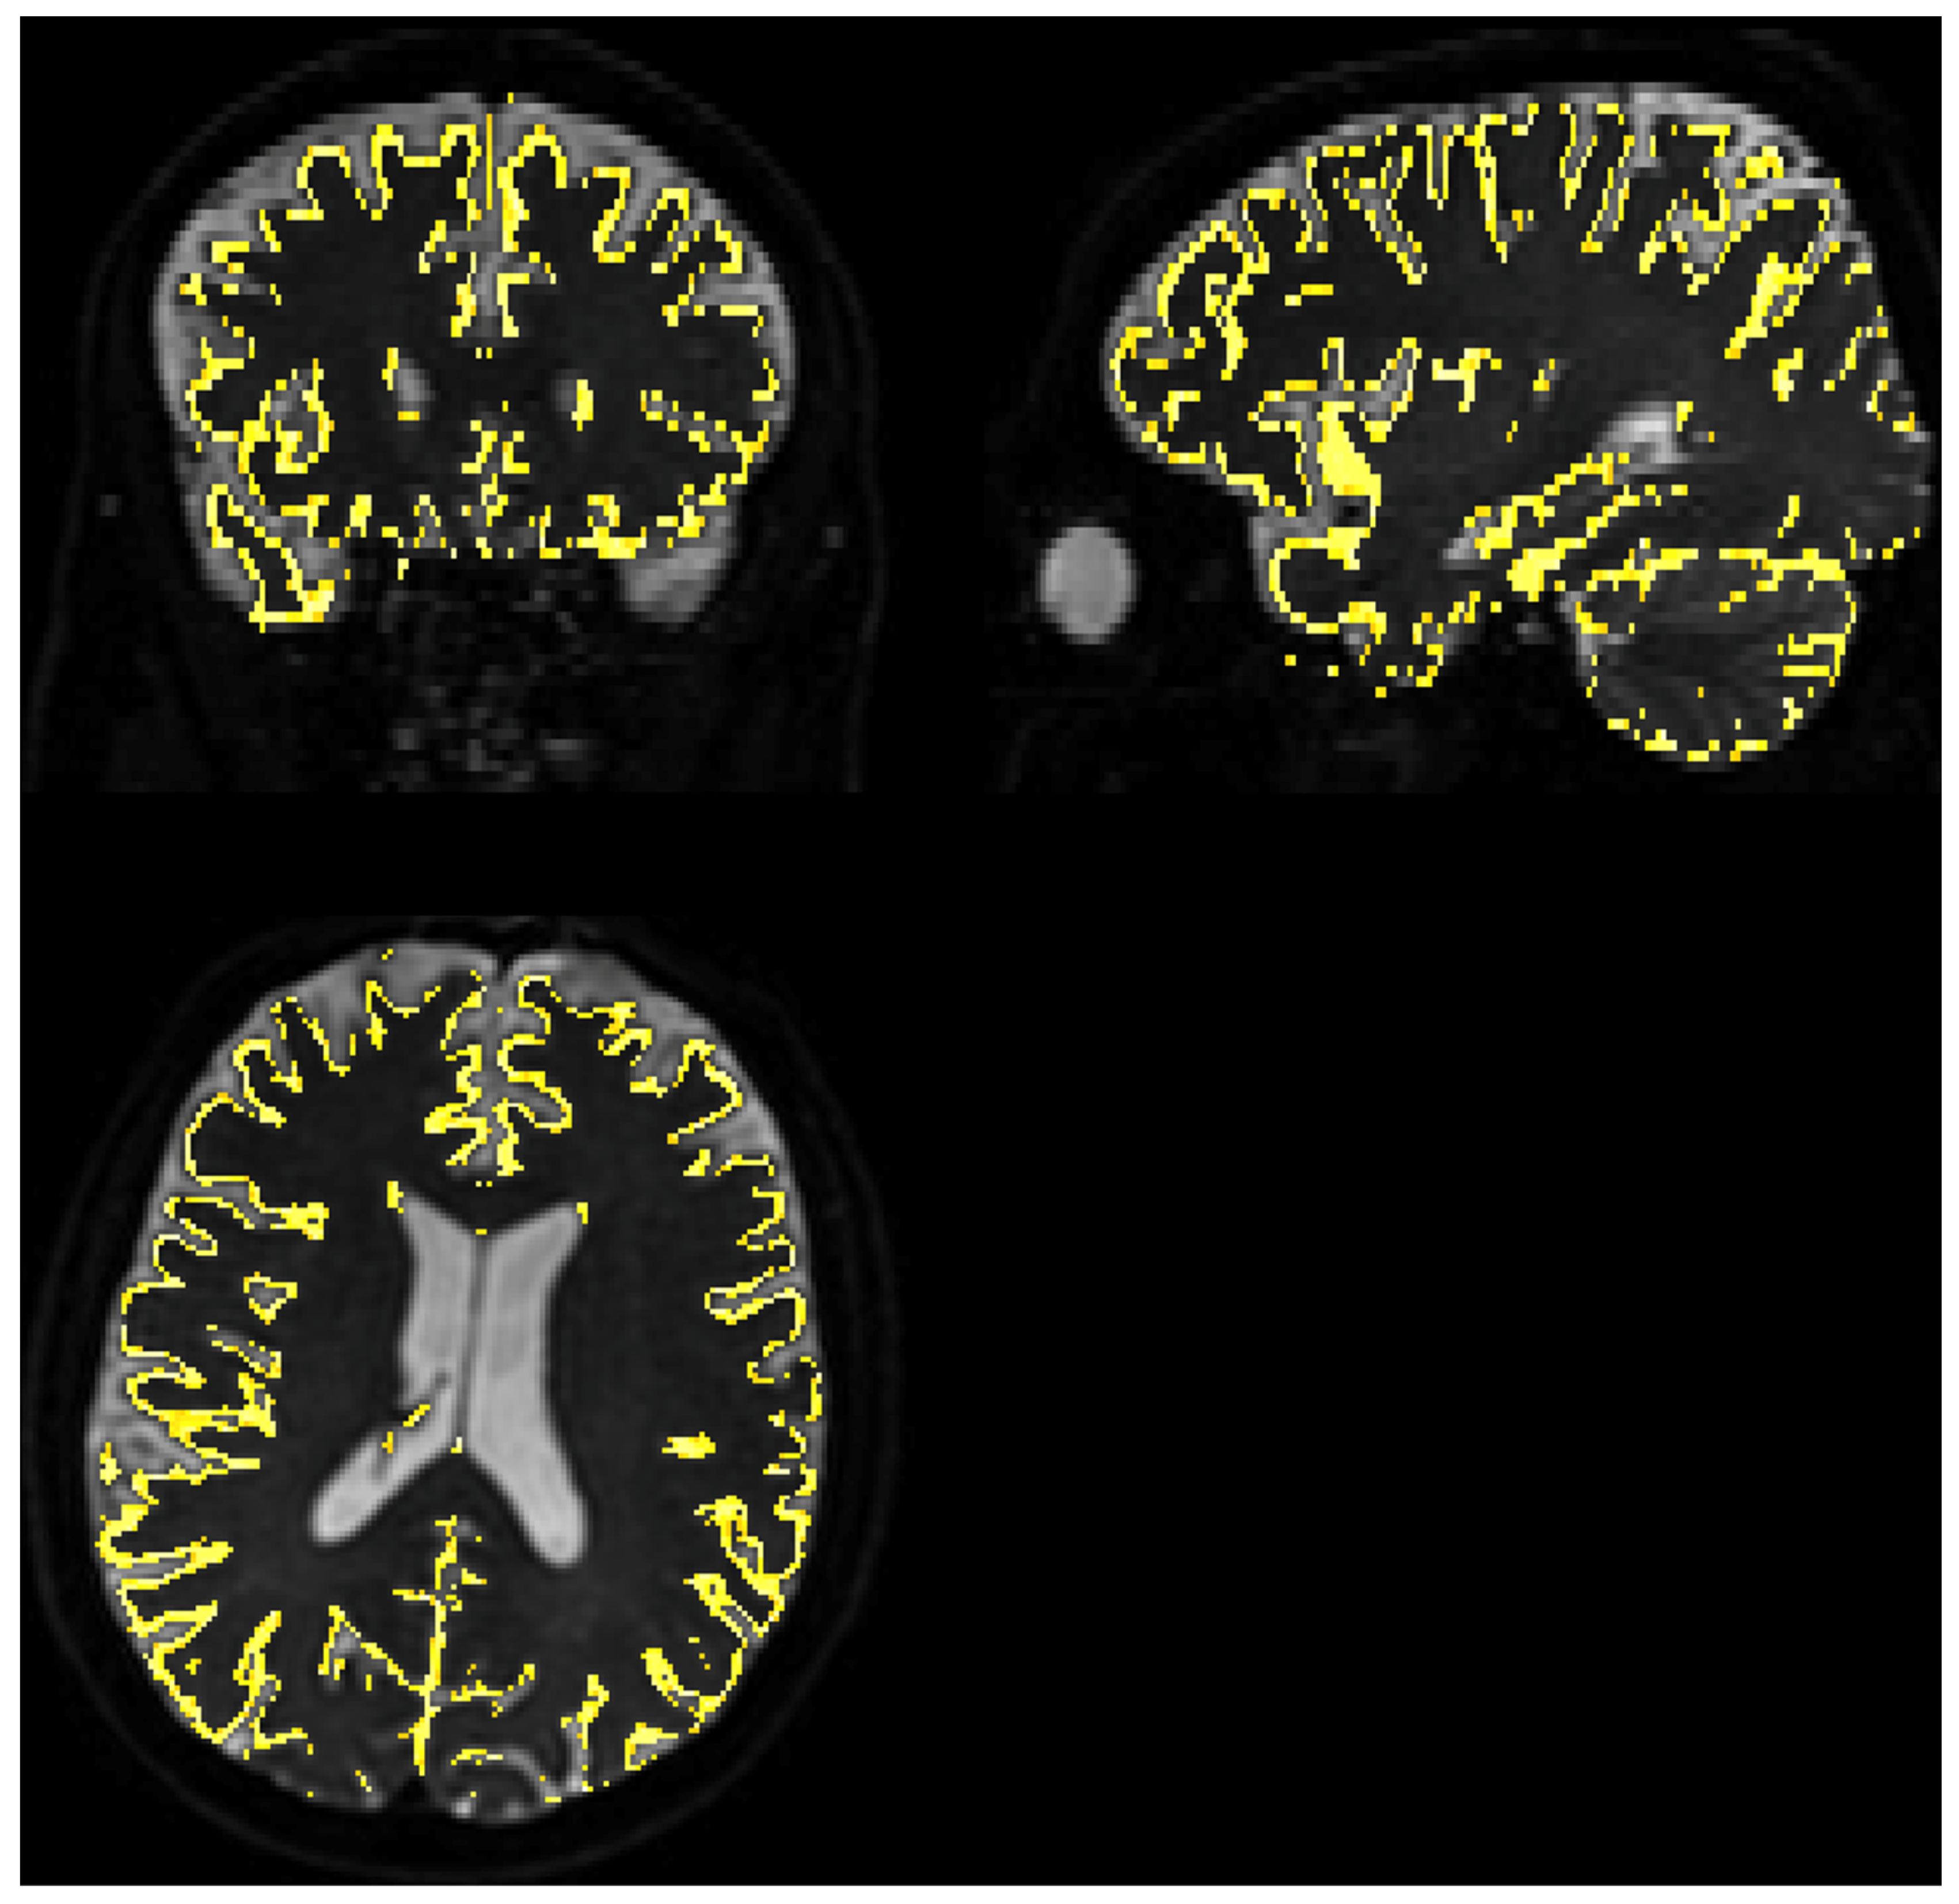

3.3.1. Quality of Matching Subject IVIM DWI Data to T2 MNI Template